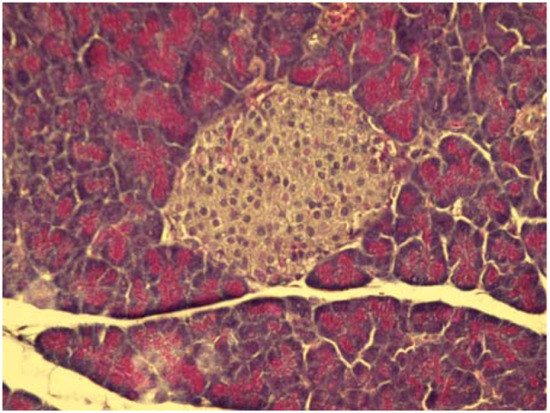

2.4. Cytoprotective effect against alloxan-induced diabetes

3.7. Cytoprotective effect against alloxan-induced diabetes